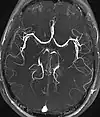

| Magnetic resonance angiography (MRA) and venography | Time-of-flight | TOF | Blood entering the imaged area is not yet magnetically saturated, giving it a much higher signal when using short echo time and flow compensation. | Detection of aneurysm, stenosis, or dissection[37] | ![]() |